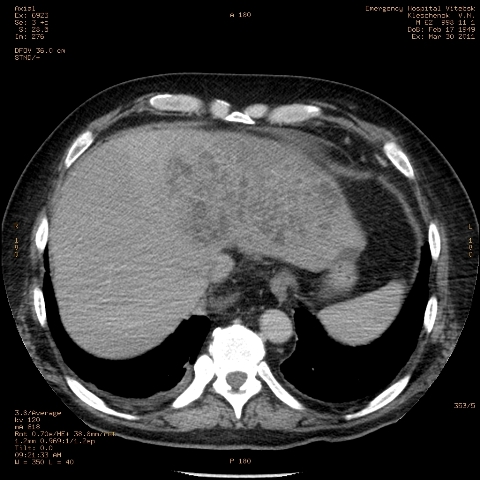

при исследовании органов брюшной полости по поводу абсцесса печени, в нижнем этаже средостения выявлено образование неоднородной плотности (-5-+25), при в/в контрастировании - не контрастируется, при per os - затёков из пищевода нет, неправильно овальной формы. предположительно киста перикарда? спасибо за помощь!

Может быть enteric duplication cyst. Как бы есть грыжа жира hiatal. И что с печенью? Мало срезов.